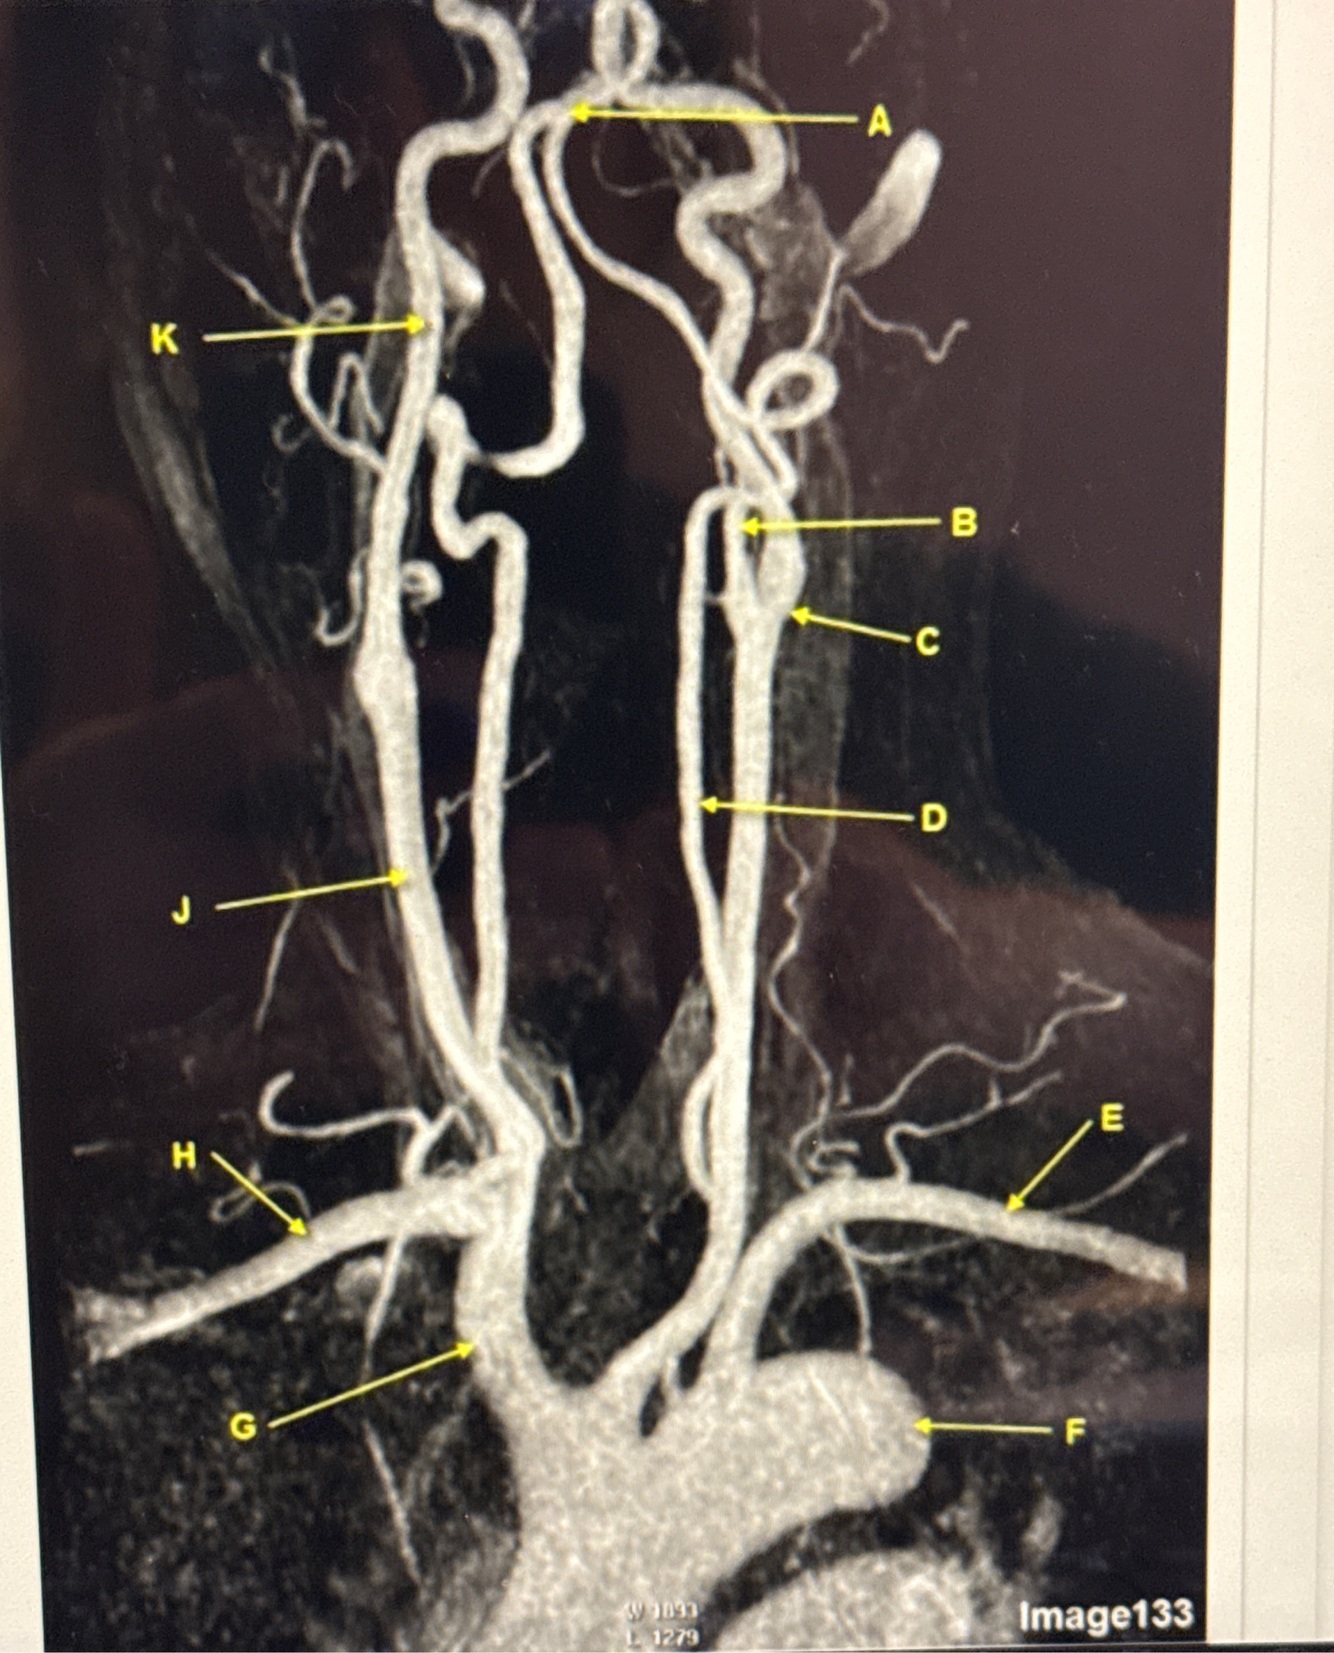

Q

What kind of MR image

A

MRA EXTRACRANIAL CIRCULATION

Letter B points to

Letter J points to

Letter A points to the

Letter E points to the

Letter K points to the

Letter C points to the

Letter B points to the _______ and letter D points to the ______

B. External carotid artery

D. Vertebral artery

Letter E points to the _____ and letter F points to the _____

E. Left subclavian artery

F. Thoracic aorta

Letter G points to the _____ , letter H points to ______ and letter J points to the

G. Brachiocephalic

H. Right subclavian artery

J. Common carotid artery

Letter K points to the ________,

K. Internal carotid artery